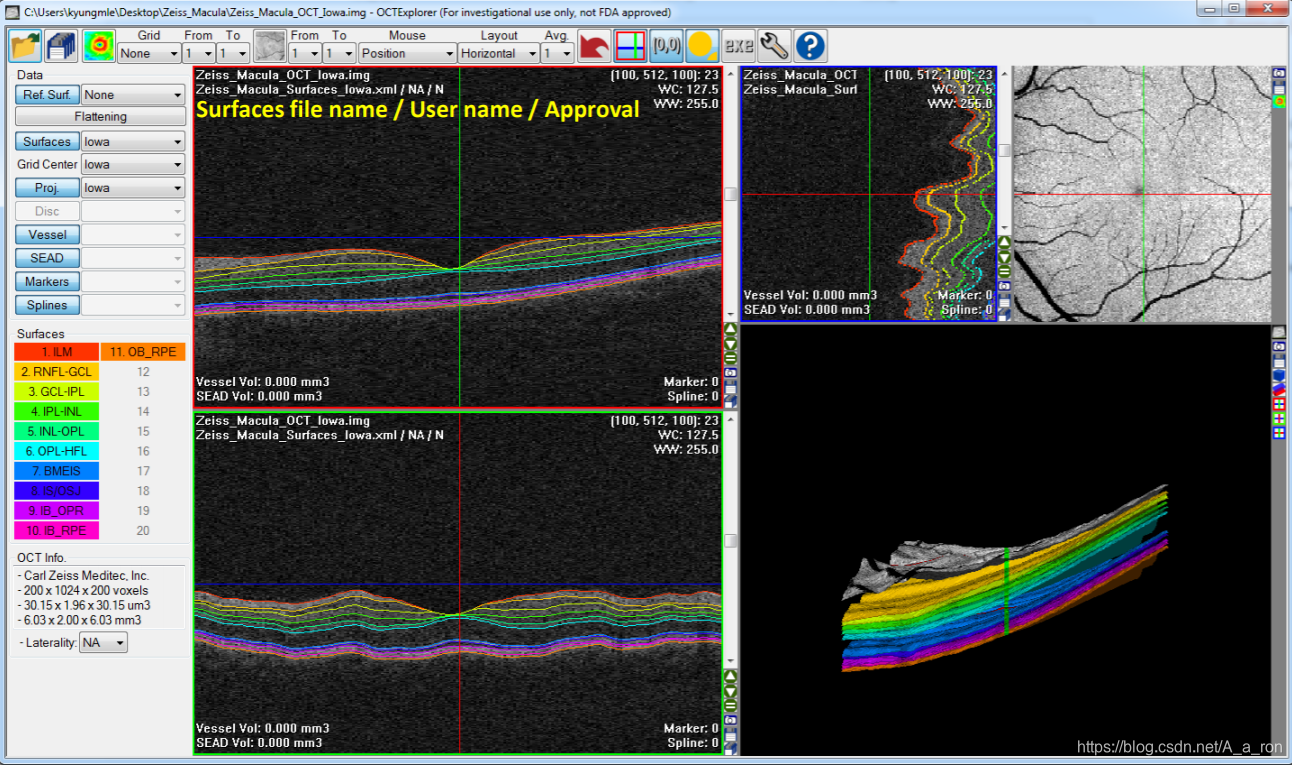

2. OCTExplorer

该软件由The Iowa Institute for Biomedical Imaging开发并维护,其包含了一系列的用于OCT影像处理的算法(目前仅支持windows平台)。软件持续得到更新,目前已经到了5.0.0版本。想要下载的话,只要同意相关的协议条款即可。同时,该软件也配置了较为详细的用户说明手册,对用户还是挺友好的。

视网膜层次分割:

更多细节和使用步骤详见用户说明手册